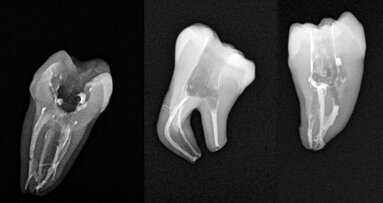

A 3D printed lower incisor used in instruction.

A 3D printed molar as viewed by a student under a clinical microscope.

The use of 3D printing also presents the opportunity for colleagues to help one another in a given field. For example, a dentist in possession of a patient’s radiograph could bring a printed tooth to a conference or to a specialist and could, together with others, develop a technique for the procedure before commencing clinical work. This is most likely to happen in complicated cases.

While working with 3D-printed models, I found that students did surprisingly better when working with premolars than with molars or incisors.